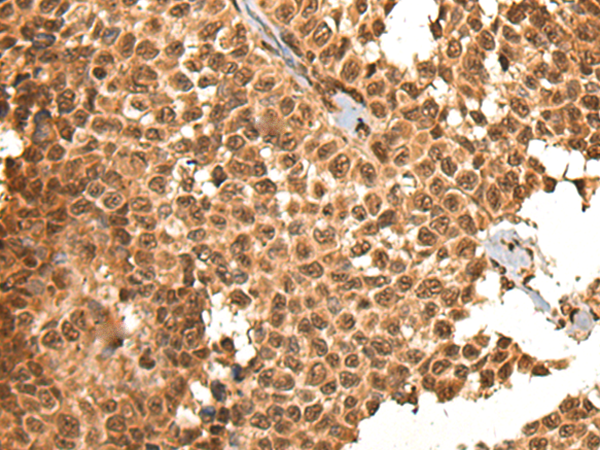

分类: 科研抗体货号: P02461别名: CALC; EFHA3; MPXPS; CBARA1应用: IHC反应种属: Human, Mouse, Rat